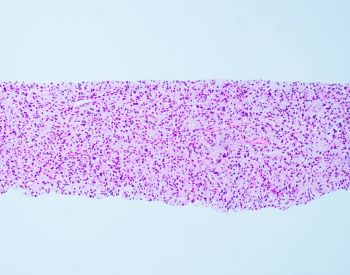

55 YOM presented with thigh mass. A biopsy was performed and showed the following lesion illustrated in the images. FISH analysis using a dual-color MDM2/CEN12 probe [Red=MDM2; Green=CEN12] was performed.

Histologically, dedifferentiated areas can be of high or low grade including area that resembles undifferentiated pleomorphic sarcoma, with pleomorphic spindle, polygonal, and multinucleated cells or with marked inflammation, or an area resembling inflammatory myofibroblastic tumor. Occasionally, the dedifferentiated component may resemble myxoid soft tissue neoplasm exhibiting myxoid stroma and delicate fibrovascular network entering the differential diagnosis with myxoid liposarcoma, myxofibrosarcoma, and low-grade fibromyxoid sarcoma. If present, the well-differentiated (lipogenic) component in dedifferentiated liposarcoma is mostly discrete showing an abrupt transition from the dedifferentiation component, but the two components can be intermingled in a mosaic pattern. Nonetheless, in small biopsies, only one component may predominate.